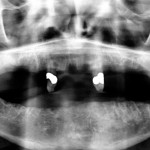

Riabilitazione implantare dopo exeresi di cancro orale in pazienti radiotrattati: follow-up a 5 anni

Riassunto

Obiettivo. L’obiettivo primario del nostro studio è quello di valutare, con un follow-up a 5 anni, il successo e la sopravvivenza degli impianti inseriti...